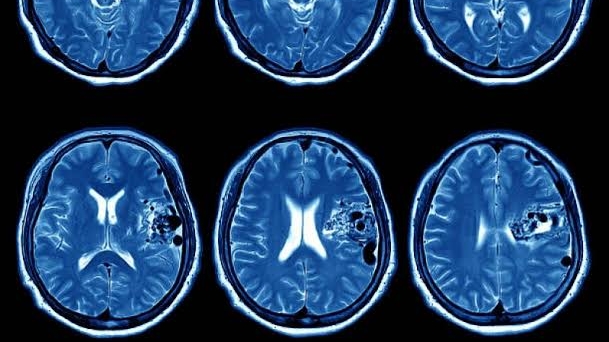

Avanço contra Câncer de Cabeça e Pescoço com Imunoterapia

Um Marco na Oncologia Um ensaio clínico global revelou que o pembrolizumabe, um medicamento imunoterápico, mantém o câncer de cabeça… Leia mais

Leia maisPesquisadores observam redução de tumores ao combinar medicamento com imunoterapia